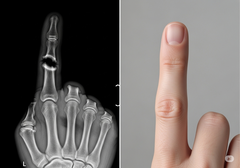

A abordagem da Bone Biologics está centrada na proteína NELL-1, um fator de crescimento que está naturalmente envolvido no desenvolvimento ósseo. Estudos pré-clínicos demonstraram que a NELL-1 tem a capacidade única de estimular o crescimento ósseo robusto exatamente onde ele é necessário e, ao mesmo tempo, inibir a formação de células de gordura, um problema comum com outros produtos biológicos. Essa ação direcionada pode levar a fusões mais confiáveis e a menos complicações.